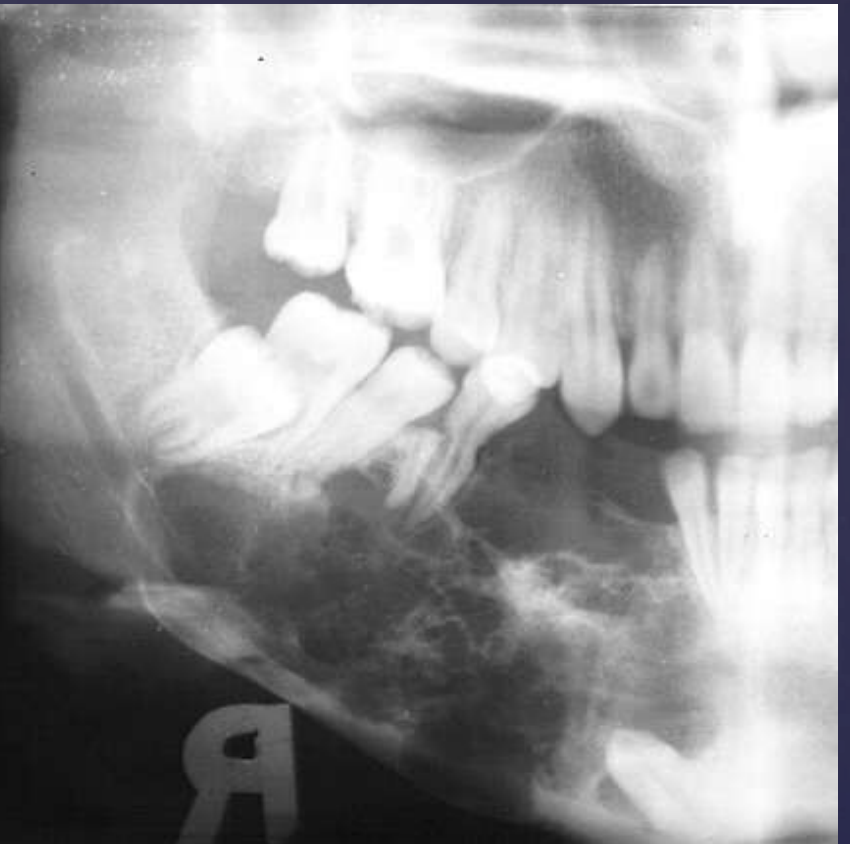

ameloblastoma

Pericoronal/mural; impacted tooth

Displacement of #32

Osseous expansion

Thinning of cortices

Displacement of inferior alveolar nerve canal